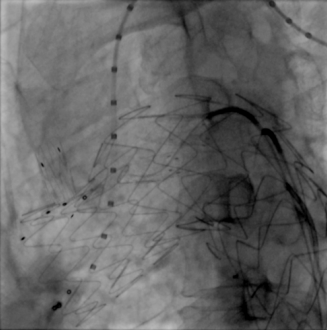

术前造影

患者平躺后,行全身麻醉,穿刺右侧股动脉、左颈总动脉与两侧肱动脉,经术前造影确认与术前CTA检查结果一致。

术前造影(正位)